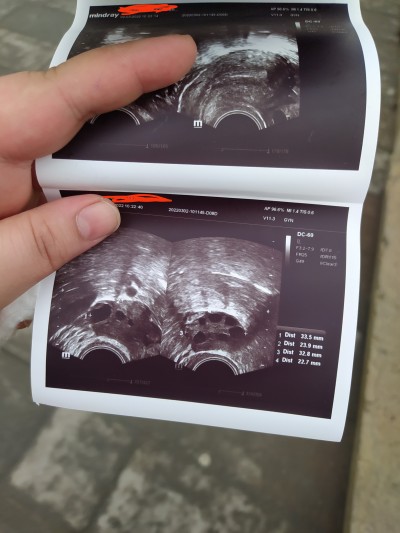

Dün troide baglı haşimatho rahatsizligim oldugunu ogrenmistim bugunde polikistik over.Bunlari yasayip gebe kalabilen var mi ? çok korkuyorum hersey ust uste geliyor

bu polikistij over yumurtalik kisti demi eger oysa arkadasimda vardi dogum kontril hapi verdi dr gecmedi ameliyatla aldirdi kisti snr bebegi oldu

Yok ikisi farklı Baby boyun annesi :) polikistik over yumurtalık bir çok kistin olması küçük küçük yumurtalık kisti sadece over kisti diye geçiyor bende de yumurtalik kisti var arkadaşınınki kaç cm di ilaçla geçmedi bende ilaç kullaniyorumda

Kuzum polikistiğin çözümü eğer kiloluysan kesinlikle zayıflamalısın bende pkos görünümü vardı ama aksine zayıftım şimdi gebeyim inşallah sende kalırsın zaten yaşında daha genç eğer kiloluysan kesinlikle zayıflaman öneririm

Polikistik var bende çatlatma iğnesiyle 2 hamilelik yaşadım

Ben canım polikistik over vardı hamile kaldım 8 ay sonra